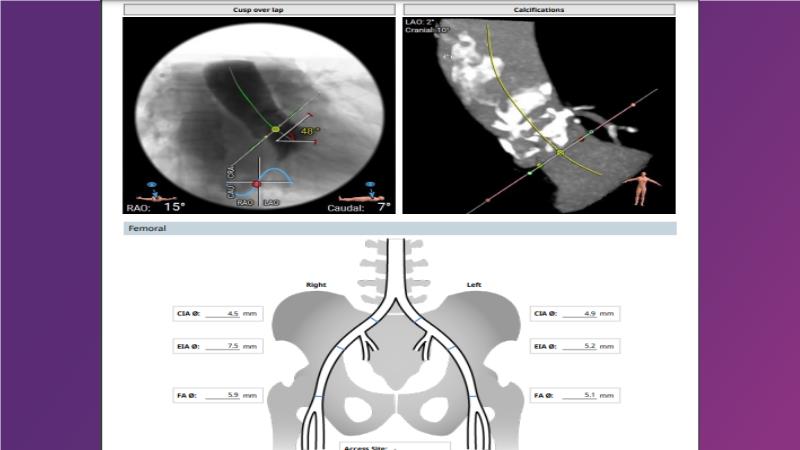

Gain expertise in selecting the appropriate TAVI device for achieving stable deployment in a 90-degree horizontal aorta. Discover techniques for ensuring smooth deliverability, particularly when navigating through tight and tortuous anatomies. Additionally, learn strategies to prepare for future coronary access, irrespective of the height of the left or right coronaries.

• To learn how to select your TAVI device in order to achieve stable deployment in 90 degrees horizontal aorta

• To be ready for future coronary access regardless of the height of left or right coronaries